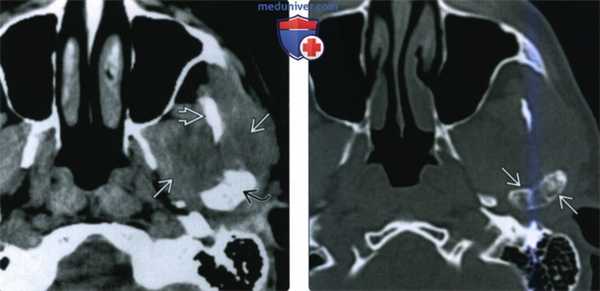

(Слева) КТ с КУ, мягкотканное окно. Другой пример хондросаркомы жевательного пространства, на этот раз без кальцификатов. Образование низкой плотности окружает ветвь нижней челюаи и распространяется вокруг венечного отростка и мыщелка.

(Справа) КТ в костном окне, аксиальная проекция. Мыщелок и шейка нижней челюсти деформированы и содержат кальцификаты. Отсутствие характерных кальцификатов в мягкотканной части опухоли делает постановку диагноза затруднительной.

(Слева) На аксиальной КТ с КУ в мягкотканном окне визуализируется гиподенсная опухоль (хондросаркома без включений кальция), окружающая ветвь нижней челюсти и распространяющаяся вокруг венечного отростка и мыщелка.

(Справа) На аксиальной КТ в костном окне определяется вздутие мыщелка и шейки нижней челюаи с наличием хондроидных кальцинатов. Отсутствие типичных для хондросаркомы кальцинатов в мягкотканном компоненте затрудняет диагностику.